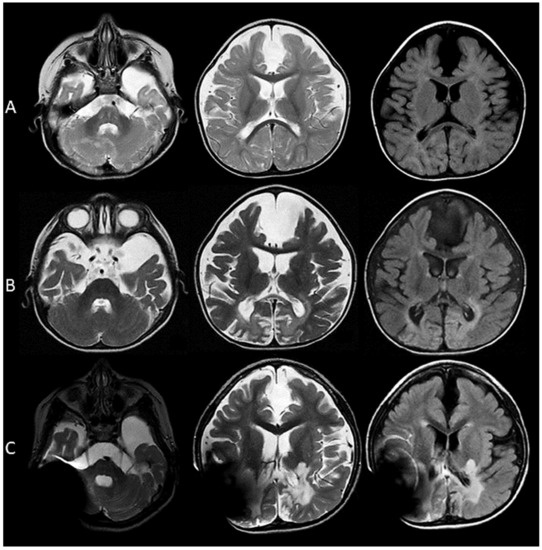

3.1.3. Images